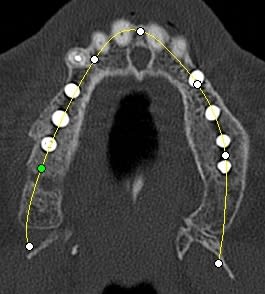

en ce qui concerne la planification j'ai une 3D kodak je me sert des cotes de l'implant Alphatech qui bien que n'ayant pas la même forme, a les mêmes dimensions.

pour votre plaisir mon ami 8 mois d'écarts

fenêtre fermée par du vitalos pas de membrane technique "grosse ouverture"